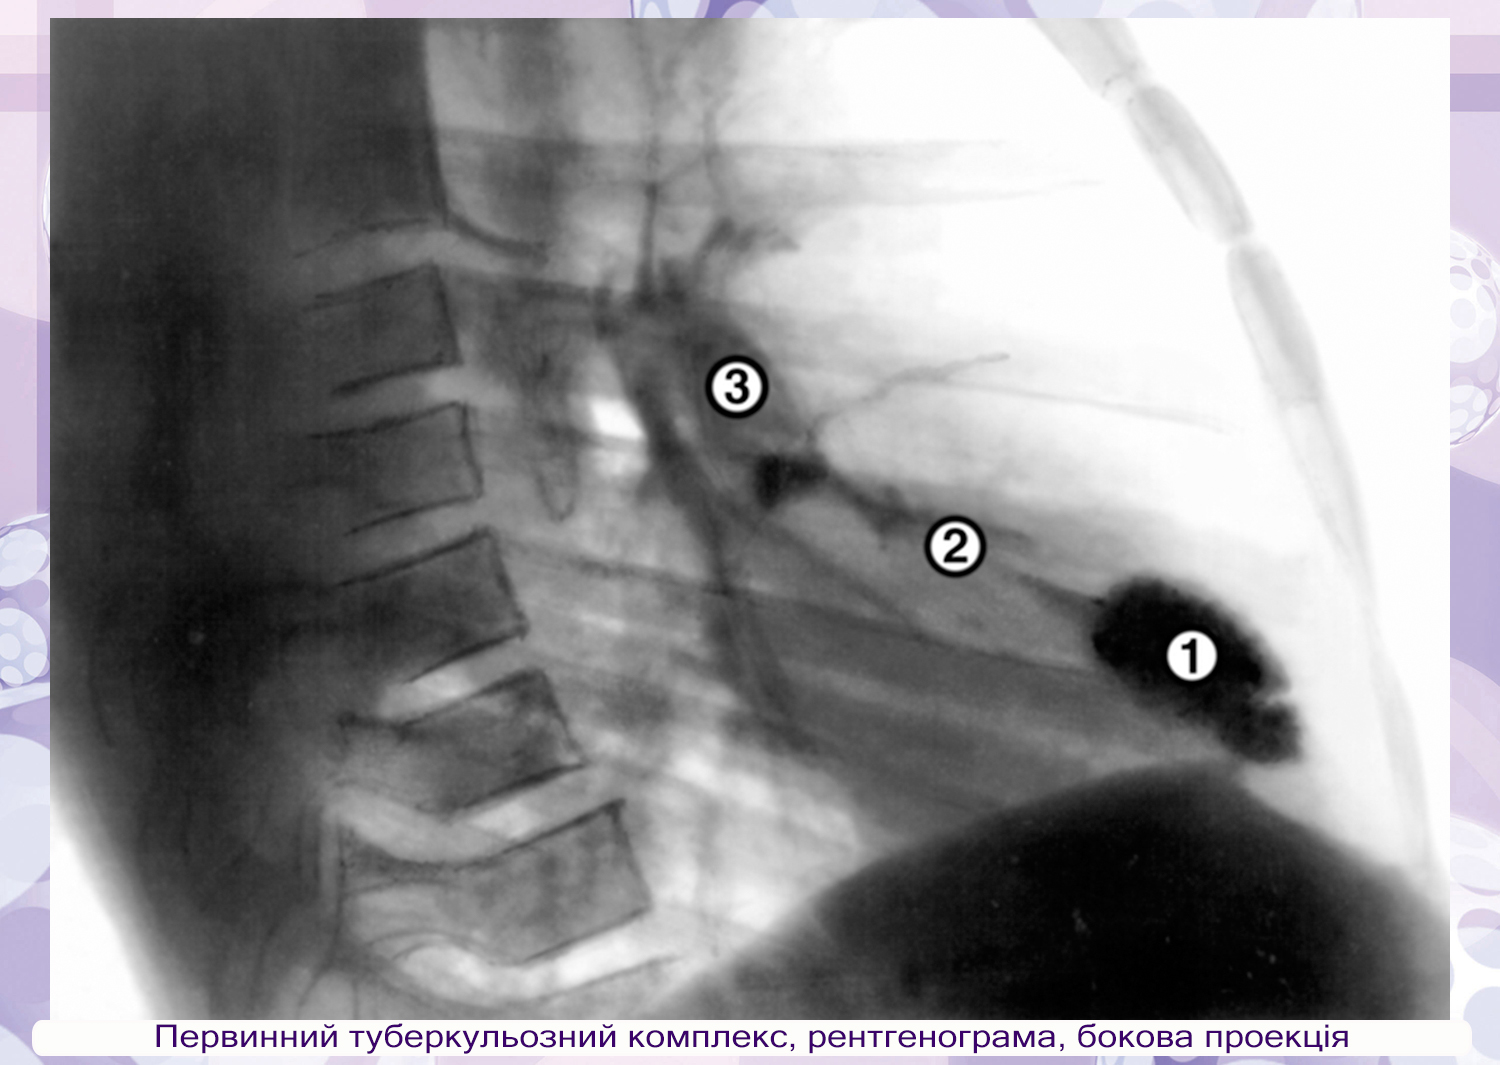

Туберкулезного бронхоаденита туберкулиновых пробы - фото презентация